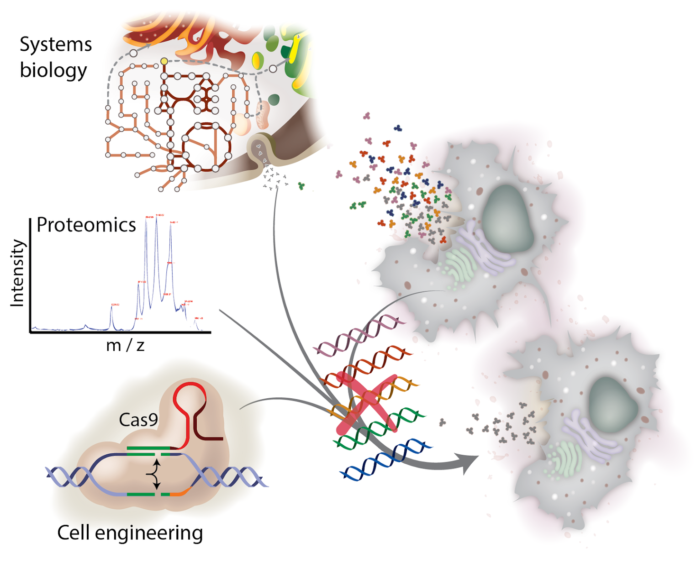

Иллюстрации из Cell Discovery: Удивительный мир науки через фотографии

Раздел: Фотоэссе